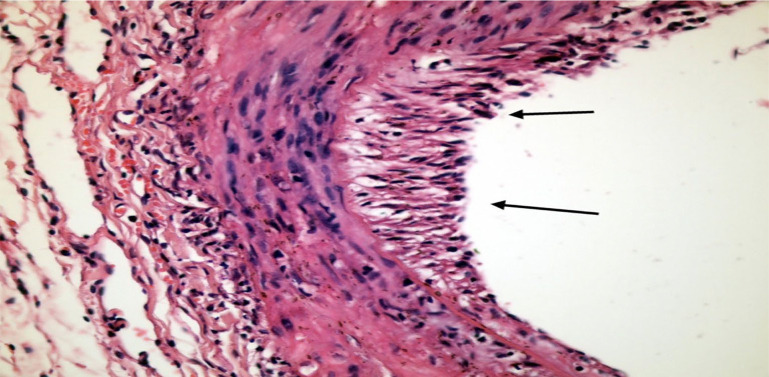

Methods: Twenty-four Wistar Albino rats were divided into four equal groups. Group A was designated as the control group and underwent laparotomy alone. In Group B, following laparotomy, the abdominal aorta was partially transected, and intimal injury was induced proximally using a 2F Fogarty catheter. Groups C and D received 20 mg/kg and 40 mg/kg of P. ginseng, respectively, and both groups underwent the same procedure as Group B. Two samples were collected from all rats with aortic injury: one from the primarily repaired aortic segment and another from the aortic segment with intimal injury caused by a Fogarty catheter. One sample was collected from the control group. The intima and media thicknesses of the collected aortic samples were histopathologically evaluated.

Results: No significant intimal hyperplasia was observed in the primarily repaired aortic segments, and P. ginseng did not have significant effect in these segments (p=0.394 and p=0.580, p=0.180, p>0.05). However, significant intimal hyperplasia developed in the aortic segments with injury induced by the Fogarty catheter (p=0.012, p<0.05). High-dose P. ginseng (40 mg/kg) significantly reduced intimal hyperplasia in these segments (p=0.036, p<0.05), while the low dose (20 mg/kg) did not show statistically significant effect (p=1.000, p>0.05).

Conclusion: Our study results showed that P. ginseng reduced intimal hyperplasia in a dose-dependent manner in rat abdominal aortas.